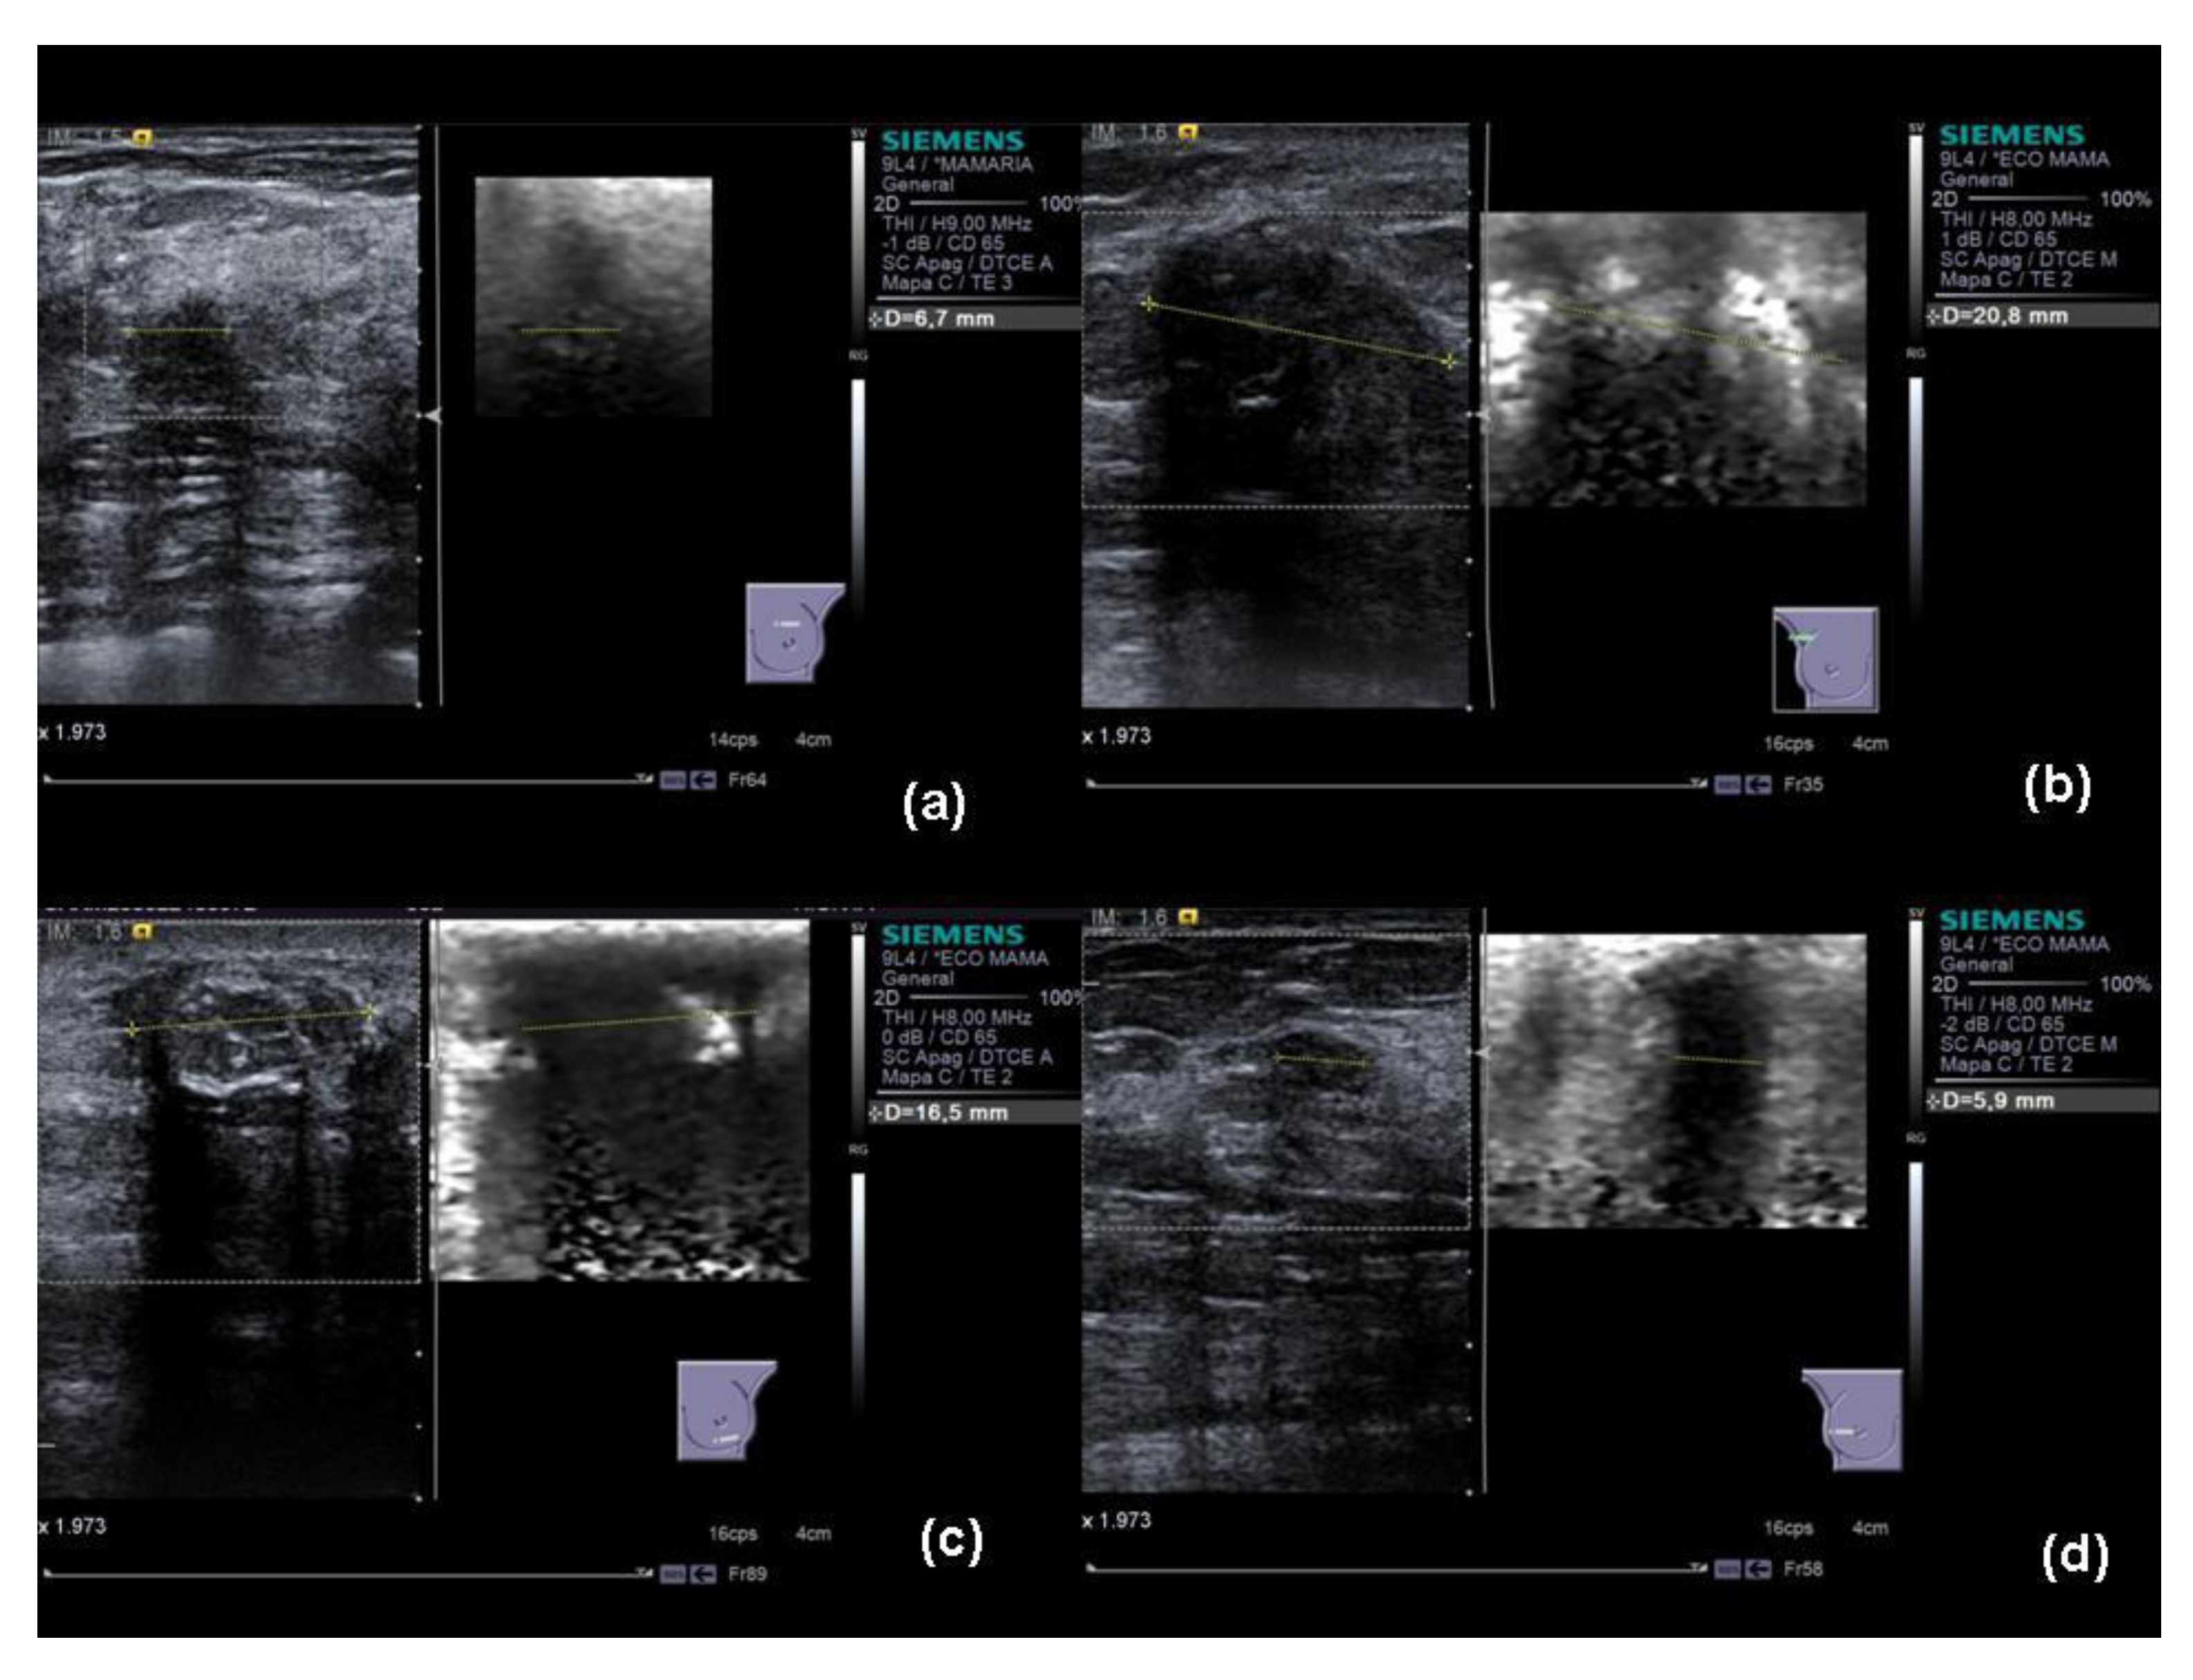

2.2. Evaluation with Elastography

- Pattern 1: Elastogram with a deformable homogenous pattern (not stiff).

- Pattern 2: Elastogram with a mosaic pattern (with deformable and non-deformable areas).

- Pattern 3: Elastogram with a pattern in which a deformable peripheral area (not stiff) with a less deformable central area (more stiff) is observed.

- Pattern 4: Elastogram with a non-deformable (stiff) homogeneous pattern with a lesion periphery with normal characteristics.

- Pattern 5: Elastogram with non-deformable homogeneous pattern (stiff) with a non-deformable lesion periphery.